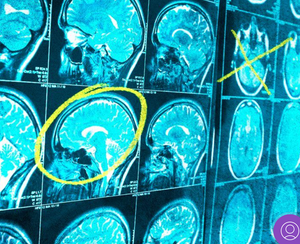

In 10 seconds? The first steps to test a cancer therapy in humans with much fewer side effects are underway. With this technology, drugs are activated by ultrasound once they reach the targeted tumour in the body, causing minimal harm.

Why is this important? Conventional anticancer approaches involve the use of invasive methods: operations and/or chemotherapeutic drugs or radiotherapy. The latter can have strong side effects by killing not just cancerous but healthy cells too – resulting in nausea, vomiting, infections and hair loss for the patient. On top of that, cancer cells start to tolerate chemotherapy and radiotherapy after a period, reducing their effectiveness. So, researchers – including our team - have been working on less invasive and more efficient approaches and one of those is sonodynamic therapy (SDT).